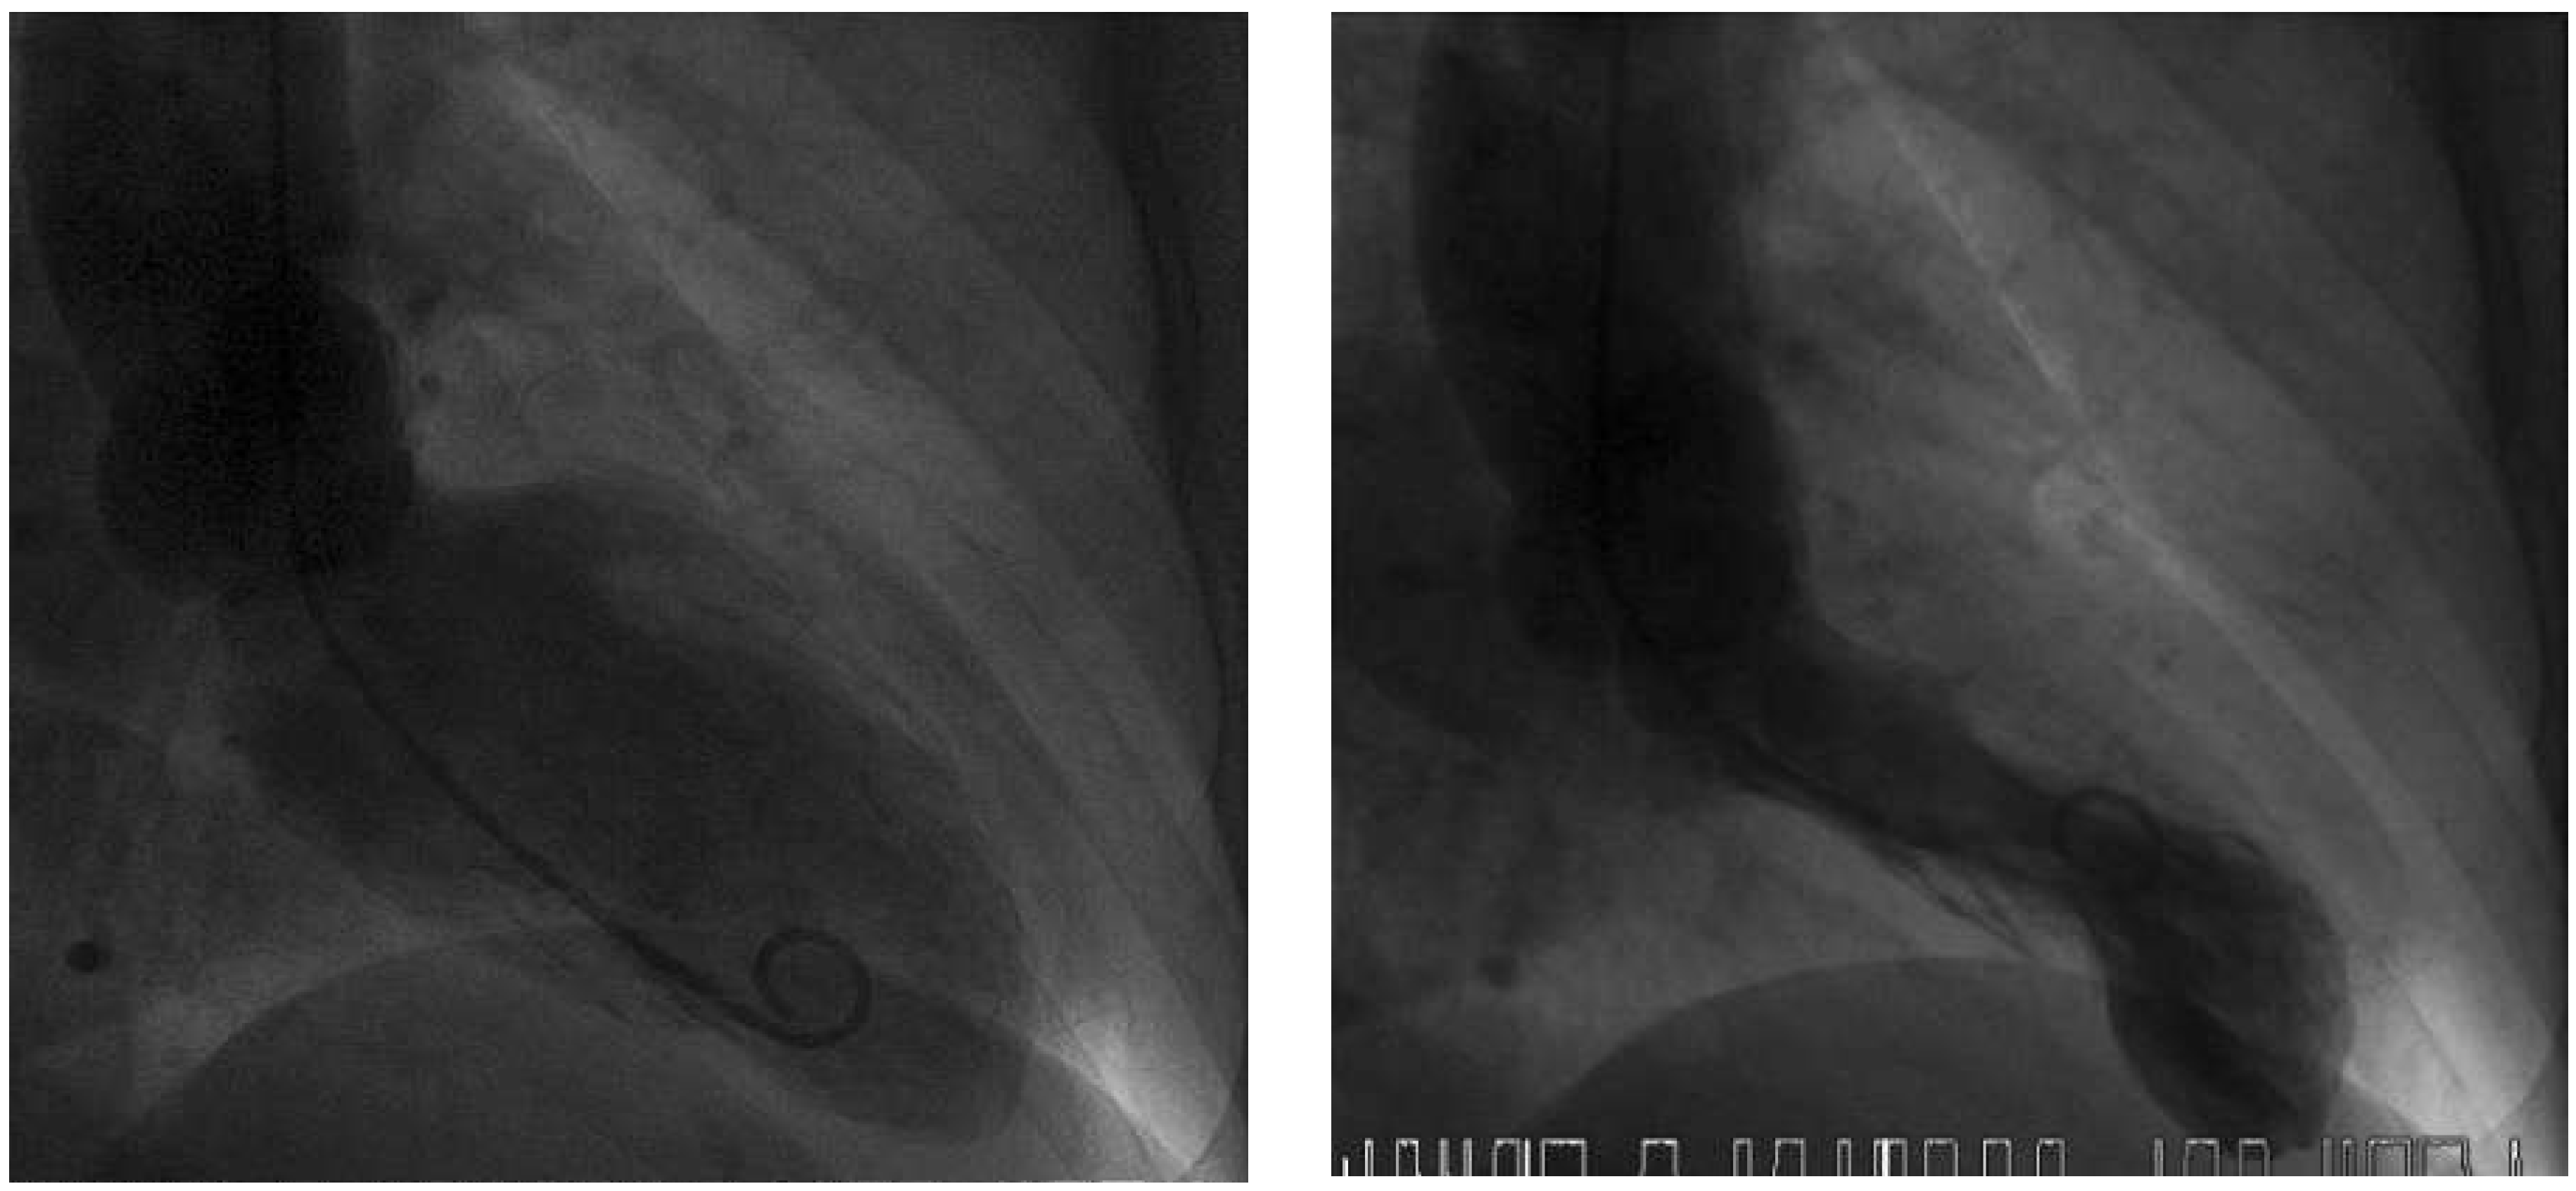

A 63-year-old female patient was admitted to our emergency department with chest discomfort radiating to her left arm. She had arterial hypertension, which had been newly diagnosed 3 months earlier and was treated with perindopril 5 mg o.d. Additional cardiovascular risk factors were a family history of coronary artery disease and the patient was an active smoker. She reported shortness of breath and dizziness, excessive sweating and a history of palpitations in the past 2 months. Recent stressful emotional or physical events were denied by the patient. She was afebrile and in sinus rhythm with a regular heart rate of 98 beats/min, blood pressure was 143/88 mm Hg and there was a loud systolic murmur. There was no exophthalmos, lid lag or pretibial myxoedema. The initial ECG showed ST elevation in the precordial leads V2–V5 (Figure 1 and Figure 2); creatine kinase (CK 250 IU/l; normal <190 IU/l) and high-sensitive troponin T (0.337 µg/l; normal <0.014 µg/l) were elevated. Acute myocardial infarction was suspected and the patient underwent emergen cy cardiac catheterisation. The coronary angiogram showed normal coronary arteries, but the ventriculogram revealed apical ballooning suggesting TTC (Figure 3). Moderate mitral regurgitation was seen on angiography and was later confirmed with transoesophageal echocardiography. Cardiac magnetic resonance imaging (MRI), performed 6 days later, showed no scar on late enhancement and myocardial oedema in T2 imaging of the left ventricular apex (Figure 4). The thyroid-stimulating hormone (TSH) level was suppressed (<0.01 mU/l; normal 0.3–4.2 mU/l) and fT4 and fT3 hormone levels were elevated (40.5 pmol/l and 14.4 pmol/l, respectively; normal 3.1–6.8 pmol/l for fT3 and 12–22 pmol/l for fT4). TSH receptor antibodies (TRAb; specific for Graves’ disease) were elevated as well, confirming the diagnosis of Graves’ disease. Remarkably, a medical check-up 3 months earlier had shown normal thyroid hormone and TSH levels. Therapy with carbimazole 15 mg b.i.d., propranolol 10 mg t.i.d. and perindopril 2.5 mg o.d. was started. The patient’s condition improved and she was discharged 4 days later. On the follow-up ECG before discharge no residual repolarisation abnormalities could be seen (Figure 5). Echocardiographic follow-up 1 month later showed normal left and right ventricular function and no residual mitral regurgitation (Figure 6). Thyroid hormone levels were still elevated, carbimazole was continued and 6 months later she underwent radioiodine therapy to control her hyperthyroidism.

Figure 3. Left ventriculogram with end-diastolic (left) and endsystolic (right) frames.Systolic apical ballooning suggests takotsubo syndrome.